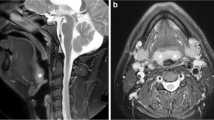

MRI mid-sagittal image of the upper airway. Highlighting the airway regions (retropalatal—from the level of hard palate to caudal margin of soft palate; and retroglossal—from caudal margin of soft palate to base of tongue) and important upper airway soft tissues (tongue, soft palate, epiglottis) and craniofacial (maxilla, mandible, hyoid) structures

Three-dimensional MRI reconstructions of the upper airway in a weight matched control subject and a patient with sleep apnea. 3D reconstructions of the key upper airway soft tissue (red = tongue, purple = soft palate, yellow = fat pads, blue = lateral walls) and craniofacial (gray = mandible) structures. Note that the size of the tongue, soft palate, fat pads, and lateral walls are larger in the patient with sleep apnea. The airway is smaller in the patient with sleep apnea